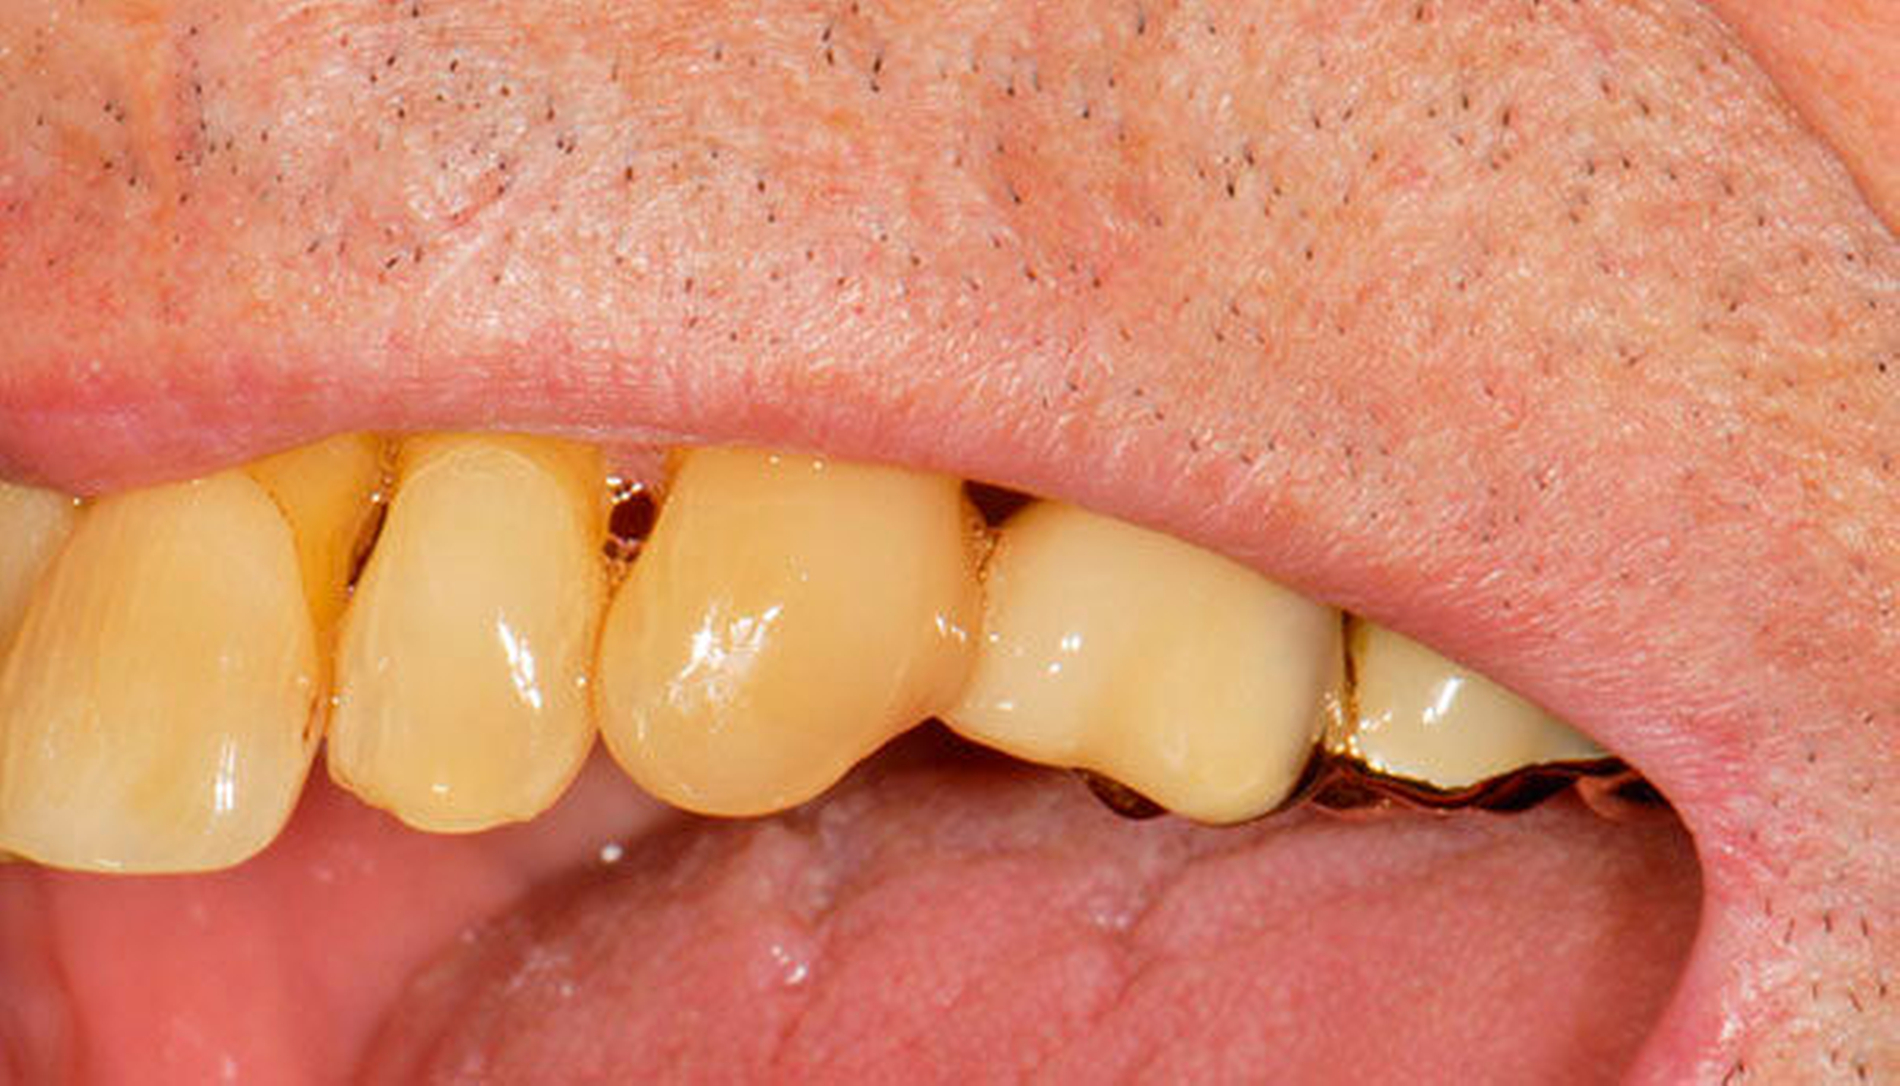

Senioren haben – wie oben ausgeführt – immer häufiger zahlreiche eigene Zähne. Im Fall von Lückenbildungen müssen diverse Behandlungsalternativen in Erwägung gezogen werden. Dazu zählen neben klassischen prothetischen und implantologischen Versorgungen auch andere Optionen (Tabelle 1). Nicht jede Lücke muss geschlossen werden. Wenn funktionell und ästhetisch keine relevanten Einschränkungen bestehen, kann auch ein Monitoring (Belassen und Beobachten) eine gute Lösung sein [Staehle, 2010; Listl et al., 2016]. Daneben kommen zuweilen Zahnumformungen und -verbreiterungen (Abbildung 1) oder direkte Freiendanhänger aus Komposit als Behandlungsmittel zum Lückenschluss in Betracht [Staehle, 2007, 2009, 2010, 2012, 2017; Staehle et al., 2014, 2015a, b; Frese und Staehle, 2018]. Schließlich ist für Patienten, bei denen aufwendiger festsitzender Zahnersatz nicht möglich ist und die keine herausnehmbare prothetische Versorgung wünschen, die Verfolgung des Prinzips der verkürzten Zahnreihe [Walter, 2016] zuweilen eine gute Alternative. Zur praktischen Realisierung dieses Konzepts kann heute die konservierend-restaurative Zahnheilkunde (zum Beispiel über Zahnverbreiterungen und -anhänger, eventuell in Kombination mit Schienungen) ebenfalls viel beitragen.

Abbildung 1 A-I: 84-jähriger Patient mit arterieller Verschlusskrankheit (Claudicatio intermittens)